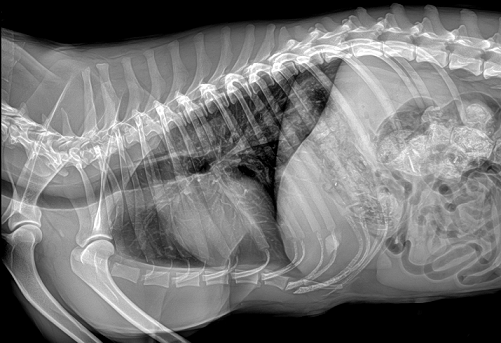

國產品牌普愛醫療寵物dr采用非晶硅平板探測器,可以令動物影像成像清晰而快速,基本上5s左右就能使動物影像清楚成像且無拖尾現象,而且分辨率高,極限空間分辨率可達到5.0Lp/mm;

普愛醫療寵物dr拍攝的高清照片

同時,寵物影像成像尺寸較大,成像尺寸可達43cm x 43cm,并且以DICOM格式儲存數據,極大的方便了醫療工作者們追蹤檢查時使用。同時還支持窗寬、窗位、放大、旋轉、正像和負像轉換等顯示功能。如果您想購買普愛醫療寵物dr,或了解具體技術參數,歡迎聯系我們。